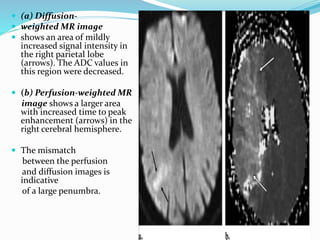

 (a) Diffusion-

 weighted MR image

 shows an area of mildly

increased signal intensity in

the right parietal lobe

(arrows). The ADC values in

this region were decreased.

 (b) Perfusion-weighted MR

image shows a larger area

with increased time to peak

enhancement (arrows) in the

right cerebral hemisphere.

 The mismatch

between the perfusion

and diffusion images is

indicative

of a large penumbra.